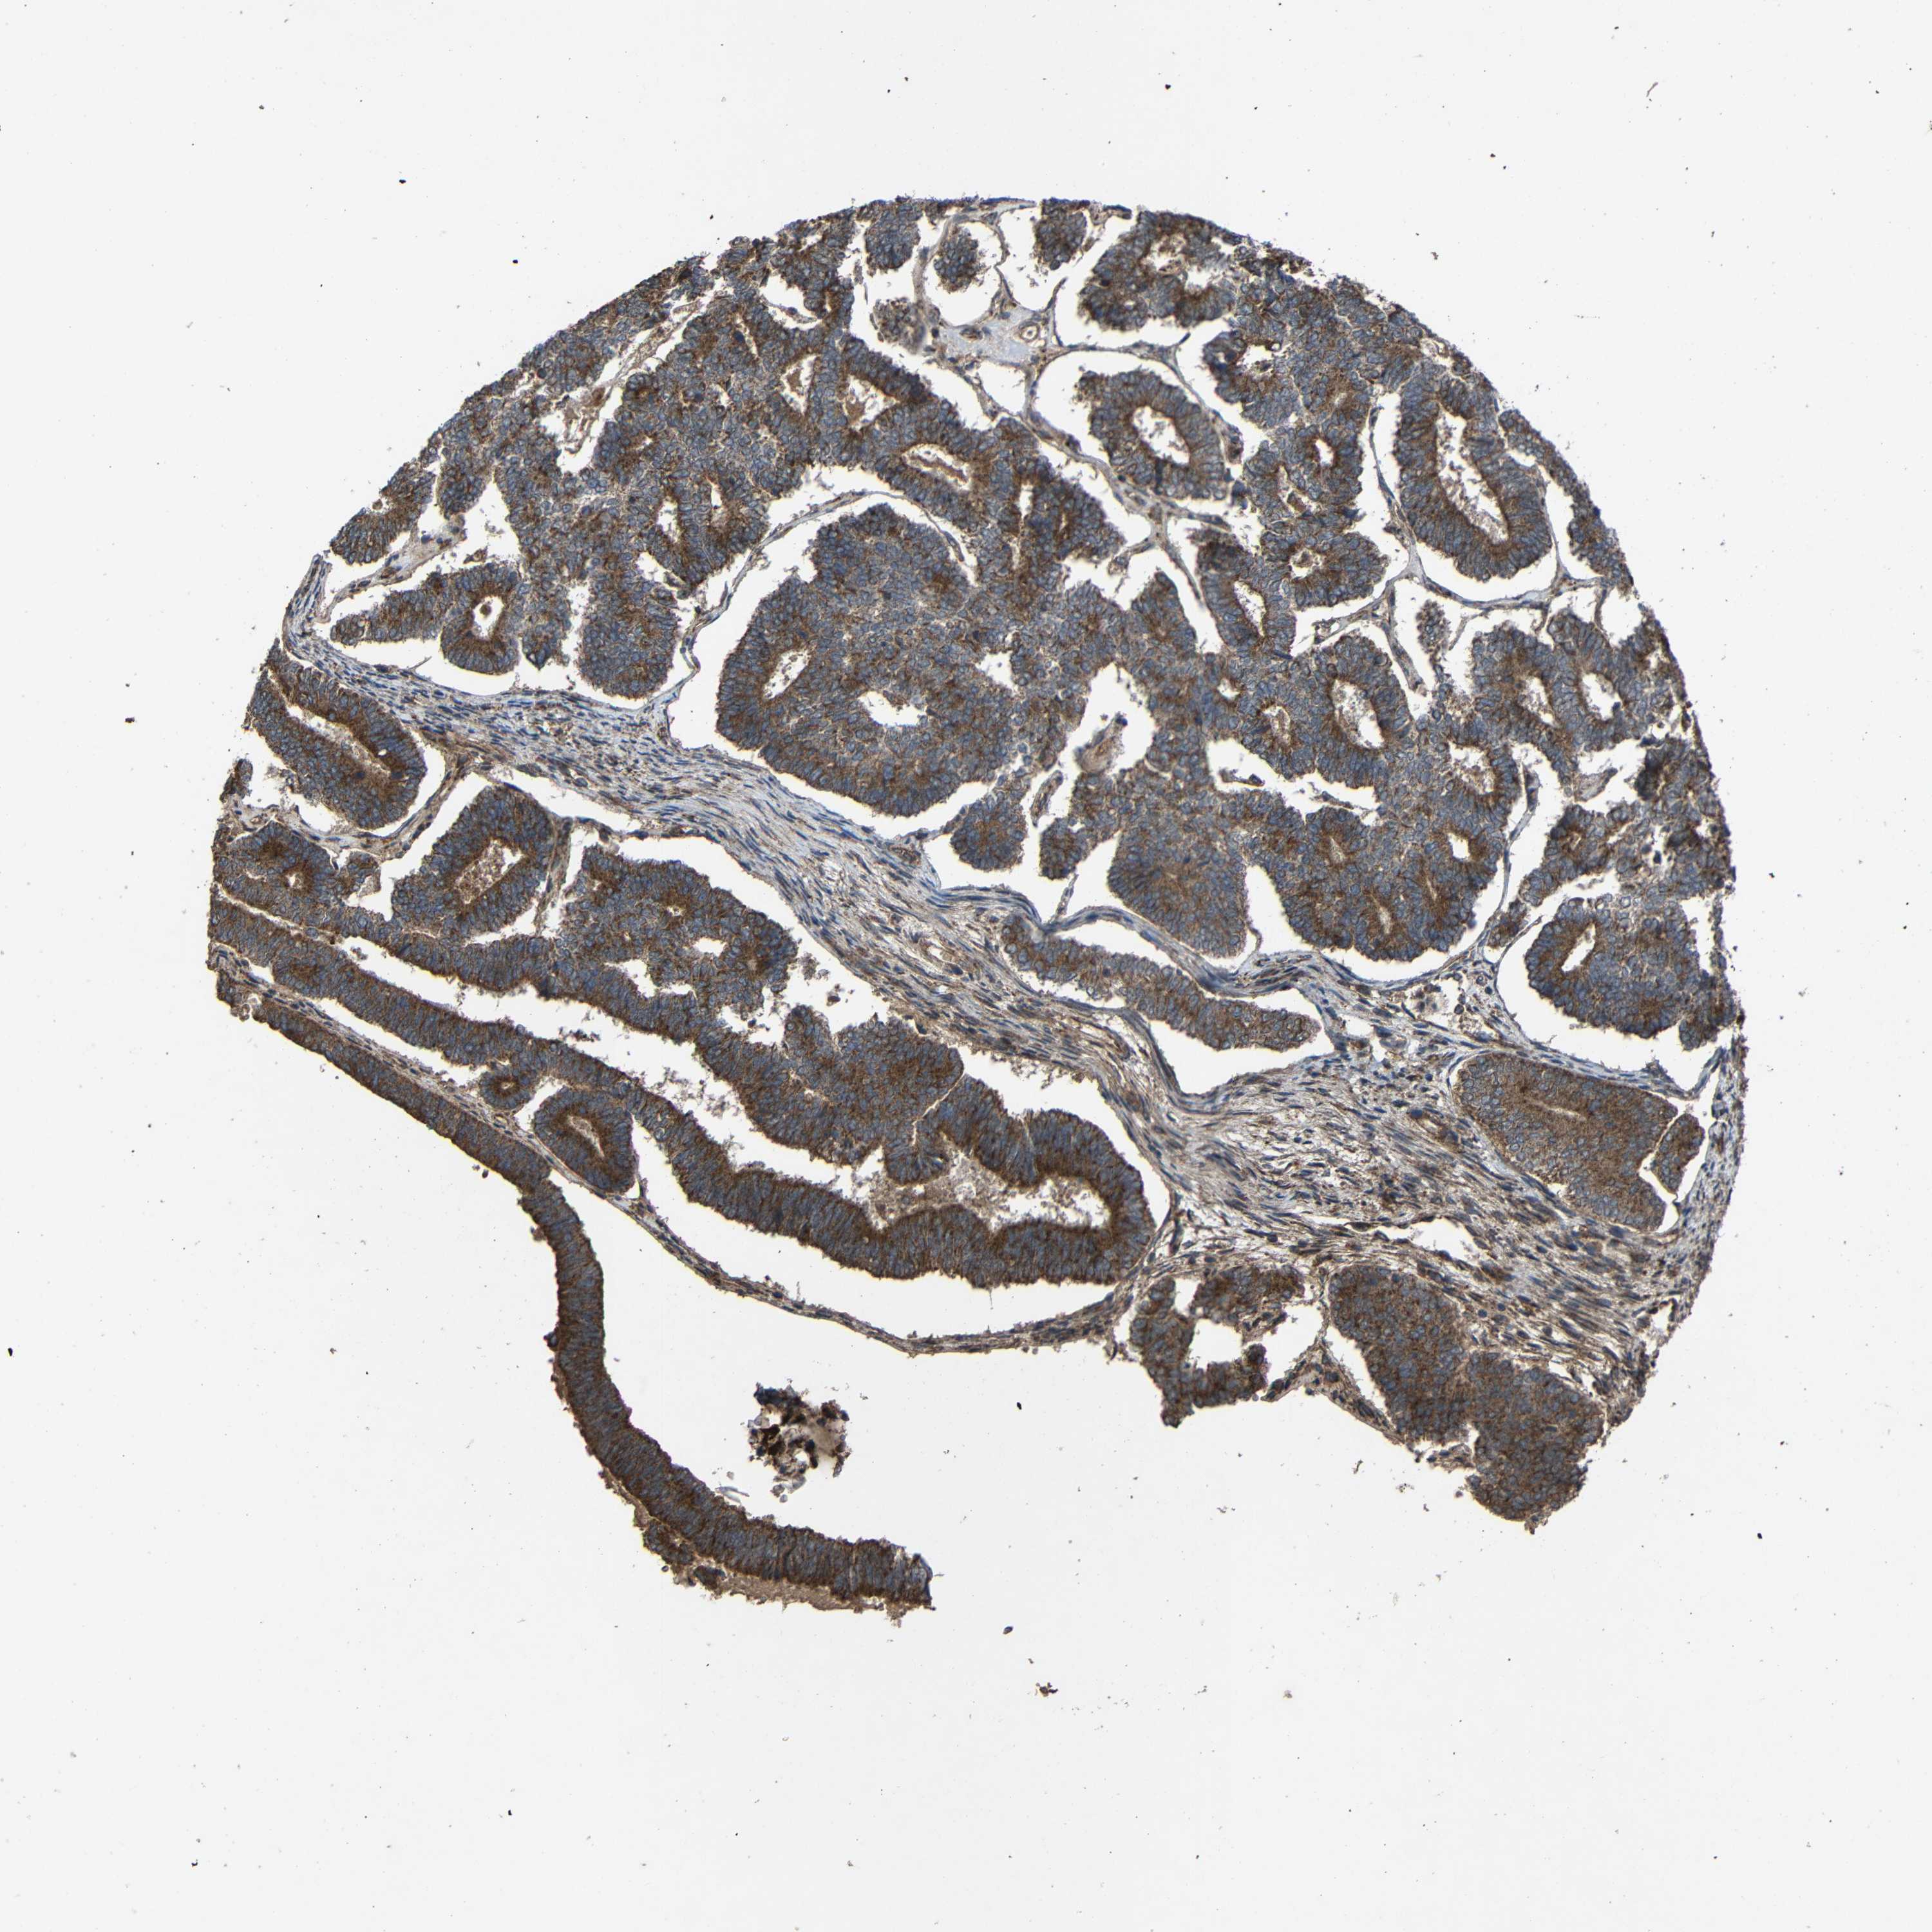

ENDOMETRIAL CANCER - Protein expressioni

A mouse-over function shows sample information and annotation data. Click on an image to view it in a full screen mode. Samples can be filtered based on level of antibody staining by selecting one or several of the following categories: high, medium, low and not detected. The assay and annotation is described here.

Note that samples used for immunohistochemistry by the Human Protein Atlas do not correspond to samples in the TCGA dataset.

Antibody stainingi

Antibody staining in the annotated cell types in the current human tissue is reported as not detected, low, medium, or high, based on conventional immunohistochemistry profiling in selected tissues. This score is based on the combination of the staining intensity and fraction of stained cells.

Each image is clickable and will lead to virtual microscopy that enables deeper exploration of all samples and also displays staining intensity scores, fraction scores and subcellular localization as well as patient and tissue information for each sample.

Antibody HPA011294

Antibody HPA012819

Staining

High

Medium

Low

Not detected

Intensity

Strong

Moderate

Weak

Negative

Quantity

>75%

75%-25%

<25%

None

Location

Nuclear

Cytoplasmic/membranous

Cytoplasmic/membranous,nuclear

Adenocarcinoma, NOS